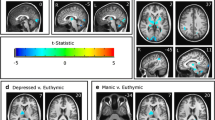

Study 2 fMRI data

Bivariate correlations between the ROIs with connections identified in Study 1 are reported in Table 3. A mixed 2 (groups) × 5 (connections) ANOVA was performed on the extracted correlations between the two groups.

Results indicated a significant main effect of connections (F[3.581, 307.992] = 13.455, p < 0.001, η2 = 0.135) and a significant interaction effect (F[3.581, 307.992] = 2.983, p = 0.024, η2 = 0.034), with no significant main effect of grou** (F[1, 86] = 0.458, p = 0.500). Simple main effects of connections indicated that the connectivity between the amygdala and fusiform was significantly greater than the other four pairs of connectivity (p < 0.001 compared to AMG–IFG and AMG–PON, p = 0.001 compared to AMG–PUL and PREC–PON; see Table 3). On the other hand, amygdala–IFG connectivity was significantly lesser than the other four pairs of connectivity (p < 0.001 compared to AMG–FUS and PREC–PON, p = 0.004 compared to AMG–PON and AMG–PUL; see Table 3). Post-hoc independent-samples t-tests were carried out to address the interaction between groups and connection. Among the five connections, only amygdala–pons connectivity remained significant after multiple comparisons (t[86] = −2.980, p = 0.004), with MDD patients exhibiting significantly greater connectivity than the HCs. Spearman’s rho correlation of the rs-FC between the amygdala and pons with the HAM-D scores also revealed a significant correlation across both groups (r[88] = 0.222, p = 0.037). Within the MDD group, the rs-FC between the amygdala and pons was also significantly correlated with the duration of illness in months (r[49] = −0.35, p = 0.014). The correlation with the number of depressive episodes (r[49] = 0.28, p = 0.05) could be considered marginally significant.

In order to validate the functional implication of the amygdala–pons connectivity in MDD, a confirmatory stepwise logistic regression was performed on the five pairs of connectivity to investigate whether they could statistically predict the MDD grou**. We found that the amygdala–pons connectivity was the only and significant statistical predictor of MDD grou** (b = 4.783, se = 1.780, p = 0.007), suggesting it to be a strong indicator of depression.

All preprocessing procedures were carried out using the CONN toolbox (RRID:SCR_009550) release 18.b 91 and SPM12 (7771; Wellcome Center for Human Neuroimaging, Institute of Neurology, UCL, http://www.fil.ion.ucl.ac.uk/spm; RRID:SCR_007037). Preprocessing was computed using the standard pipeline implemented in the CONN toolbox. Correction for participant motion, susceptibility distortions, and slice timing were first performed on the functional data. These functional images were then aligned to standard MNI space and smoothed using an 8-mm full-width half maximum Gaussian kernel. Signals from cerebrospinal fluid, white matter, and participant motion were treated as confounds and linearly regressed out92. A band-pass filter between 0.008 and ~0.09 Hz was applied to minimize other potential sources of noise. For each resting-state fMRI scan, the quality of the images before and after preprocessing was visually inspected to confirm no ghosting, motion artifact, or signal dropout was observed across the brain and within our ROIs. Our research aimed to examine how the normal processing of sad affective information is altered among patients with MDD. Therefore, we selected ROIs based on the neural correlates of processing sad stimuli identified in Study 1 (Fig. 5a, blue arrows). To ensure that previously identified regions were fully represented, the ROIs utilized in this analysis were well-defined anatomical masks extracted from atlases93,94,95,96,97. The regions included the pons, precuneus, bilateral amygdala, bilateral fusiform, bilateral IFG, and bilateral pulvinar. The CONN toolbox was then used to perform seed-to-seed bivariate correlations by examining the temporal correlations between the BOLD signals extracted from each pair of ROIs.